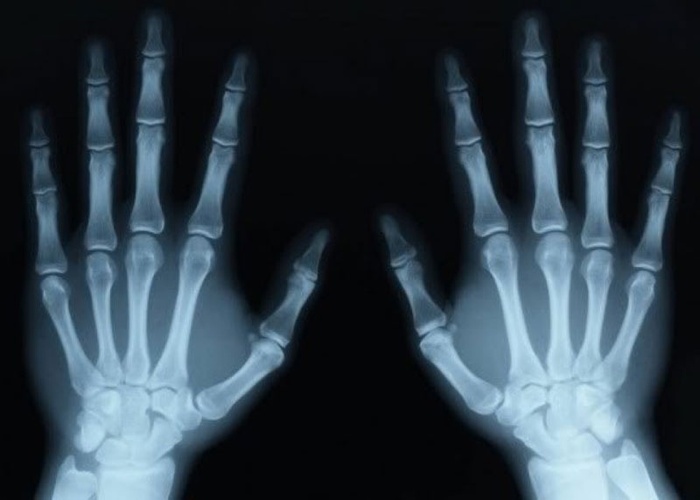

Tuổi xương là tuổi của xương, có thể xác định bằng cách đến bệnh viện chụp X-quang và chụp ảnh cổ tay trái để xác định. Đối với người trưởng thành khỏe mạnh, tuổi xương gần hoặc phù hợp với tuổi sinh học. Ở trạng thái khỏe mạnh, tuổi xương của phụ nữ sẽ bắt đầu khép lại vào khoảng năm 14 tuổi.